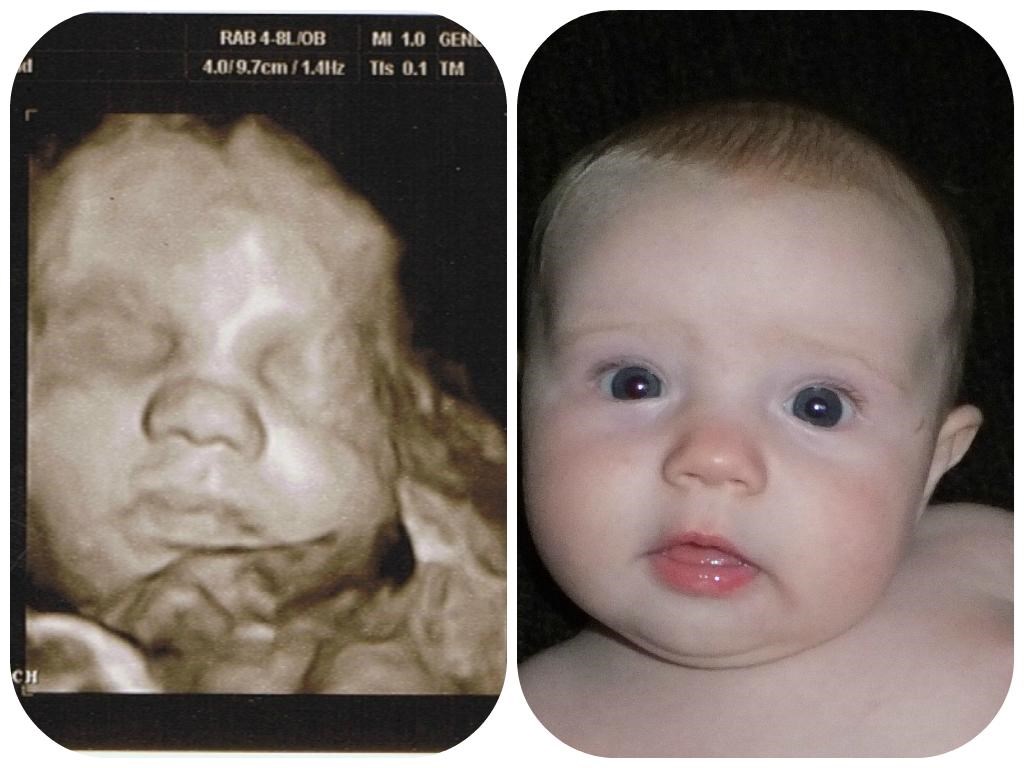

Koliko je precizan 4D ultrazvuk nerođene bebe

4D verzija je u biti obična 3D snimka, ali u realnom vremenu, bez čekanja na obradu slike.